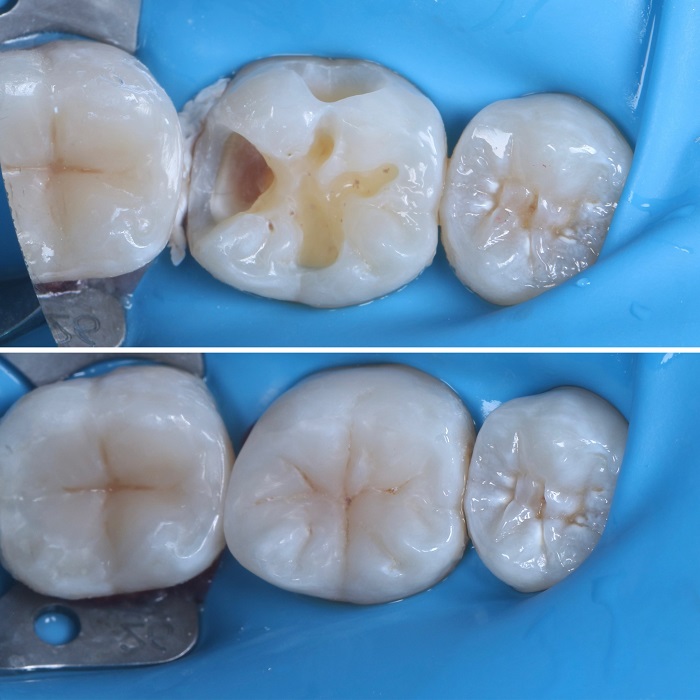

Глубокий кариес моляра

Пациент обратился с жалобами на значительное разрушение жевательной поверхности одного из моляров нижней челюсти, которое сопровождалось дискомфортом при приёме пищи. Визуально отмечалось нарушение краевого прилегания ранее установленной пломбы, потемнение тканей по краю реставрации, что указывало на прогрессирующее кариозное поражение. Осмотр подтвердил наличие глубокого кариеса с риском поражения пульпы и дальнейшего развития воспалительных осложнений при отсутствии своевременного вмешательства.

Старая пломба и пораженные кариесом ткани были полностью удалены с сохранением здоровых структур зуба. Образовавшаяся полость была очищена, обработана антисептиком и подготовлена к реставрации.

Восстановление проведено с применением композитного материала светового отверждения — послойно, с воссозданием анатомической формы жевательной и контактной поверхностей. Каждый слой тщательно полимеризован для достижения прочности и герметичности.

В завершении выполнены коррекция прикуса, шлифовка и полировка пломбы до достижения гладкости и комфорта при жевании.

Восстановлена функция и эстетика зуба, предотвращено развитие воспалительных процессов и необходимость в более сложном вмешательстве в будущем.